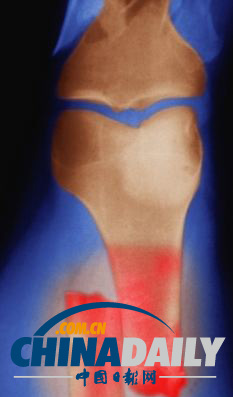

研究人員將皮膚細(xì)胞重新編排成能夠形成早期階段骨細(xì)胞的干細(xì)胞,圖為骨細(xì)胞內(nèi)部的海綿狀結(jié)構(gòu)。

研究人員首先將皮膚細(xì)胞重新編排成干細(xì)胞,這種干細(xì)胞能夠形成早期階段的骨細(xì)胞,然后再將其接種到三維支架中,同時(shí)提供營養(yǎng)刺激其生長。在經(jīng)過長達(dá)12周的培養(yǎng)后,這種由皮膚細(xì)胞轉(zhuǎn)化而來的骨細(xì)胞被移植到實(shí)驗(yàn)鼠體內(nèi),并順利形成了骨組織。在整個(gè)實(shí)驗(yàn)過程中,沒有出現(xiàn)任何可能產(chǎn)生腫瘤的現(xiàn)象。